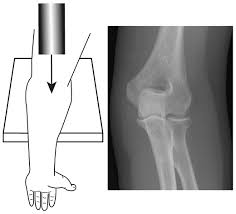

10+ Elbow Anatomy Xray. Elbow injuries have characteristic appearances. This is an online quiz called elbow xray anatomy.

A patient's guide to elbow anatomy. Normal radiographic anatomy of the elbow | radiology case human anatomy and physiology. To install xray anatomy on your windows pc or mac computer, you will need to download and install the windows pc app for free from this post.